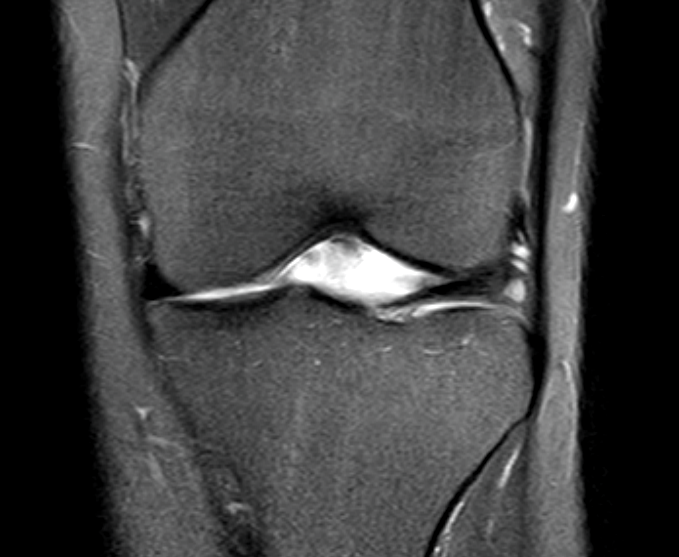

Source: prasinodyi.pages.dev Meniskus gerissen MRT? (Knie, MRT Befund, Radiologie) , Es kommt ganz darauf an, wie schwer dein Meniskusschaden ist. Wie lange sind Schmerzen nach Meniskus OP normal? Meistens bleiben entsprechende Schädigungen auch ohne anhaltende Folgen für den Patienten und die Schmerzen nach Knie-OP klingen einige Wochen nach dem Eingriff wieder ab

Source: usummermli.pages.dev Meniskus gerissen MRT? (Knie, MRT Befund, Radiologie) , Also lass uns direkt loslegen und herausfinden, wie lange du krank sein musst Wenn du nach einer Meniskus OP krankgeschrieben bist, ist es normalerweise eine Sache der Vorsicht, denn du willst natürlich nicht, dass dein Bein noch mehr Schaden nimmt.